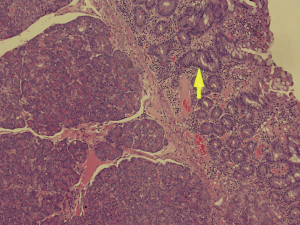

Histopathological analysis of the specimen revealed complete excision of the mass, which was reported to be benign pancreatic tissue, showing both endocrine and exocrine elements (islets of Langerhans, pancreatic acini, and pancreatic ducts) (Figures 4-9). No atypical features were seen and there was no evidence of malignancy.